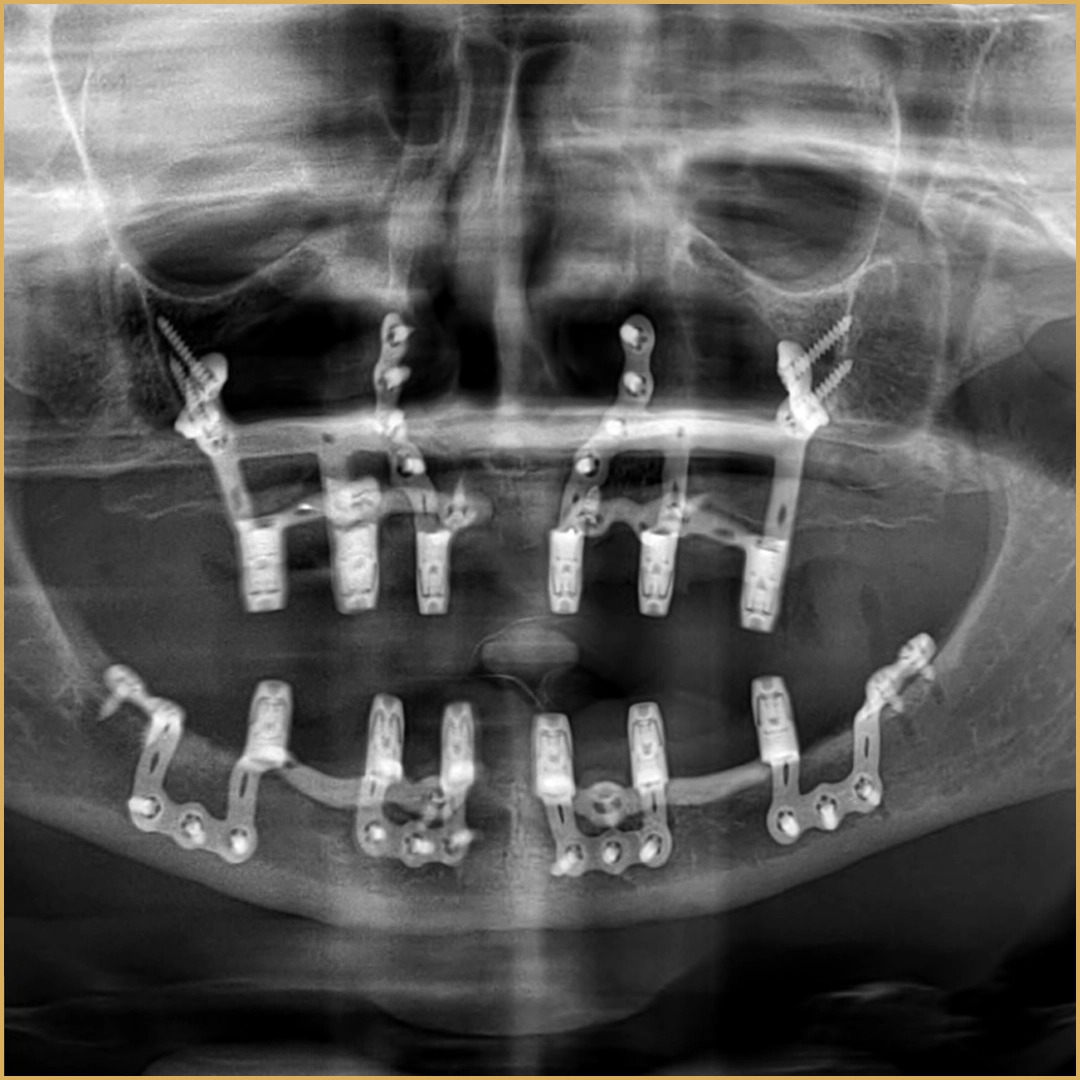

Traditional dental implants require sufficient jawbone density, leaving many patients with severe bone loss with limited options. Subperiosteal implants offer a revolutionary alternative, fitting a custom metal framework directly atop the jawbone beneath the gum line to support prosthetic teeth.

“This is a highly specialized procedure,” Dr. Alsaman explains. “Many clinics hesitate to offer it because it demands precise surgical skill and advanced digital technology. At Vitrin Clinic, we’ve perfected this technique. Our use of three-dimensional imaging and patient-specific metal frameworks ensures stability and long-term success, even for cases considered untreatable elsewhere.”

The clinic’s investment in advanced technology is key to its success. Cone beam computed tomography (CBCT) delivers ultra-detailed 3D images of the jawbone, allowing precise planning of the subperiosteal implant framework. Digital smile design software enables patients to visualize their future smile before any procedure begins.